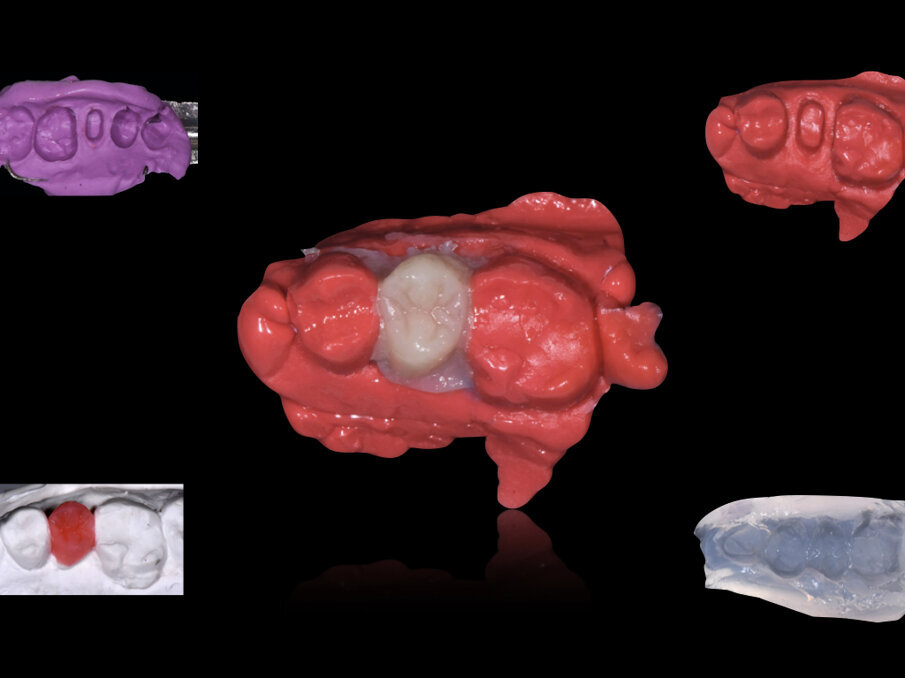

Fig. 2: Los postes individuales se disponen de forma uniforme en el espacio para el poste, a fin de ajustarlos con precisión a la geometría del conducto radicular. Un espaciador puede ayudar a la disposición uniforme de los postes individuales, para lo cual el autor eligió un pincel de aplicación Endo Tim.

Fig. 3: Fabricación en el mismo consultorio de una prótesis provisional indirecta con un composite autopolimerizable (Structur 3, VOCO) utilizando GrandioSO Inlay System (VOCO).